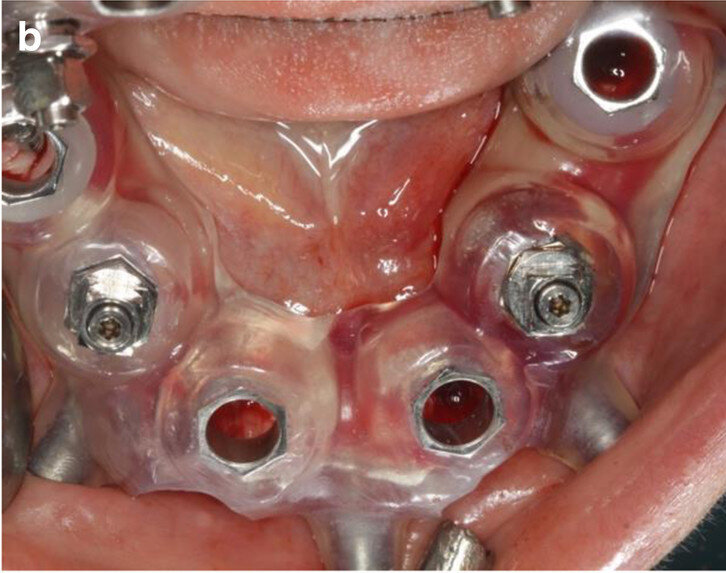

Fig. 5b: CAD/

CAM-fabricated surgical guides: tooth- and mucosa- supported (a) and implant- and mucosa-supported (b).

The two-step approach entailed the flapless, guided insertion of four posterior implants (ELEMENT RC, 4.5 × 9.5 mm; Thommen Medical), using the first surgical template, which was tooth- and mucosa-supported (Fig. 8a). The template was then removed and teeth #42 and 33, which had supported the guide, were extracted. Thereafter, the second surgical template was positioned and stabilised on the four posterior implants with the help of specific abutments and the same anchor pins (Fig. 8b), thus allowing guided placement of implants (ELEMENT RC, 4.5 × 9.5 mm) in positions #42 and 33 immediately after the extractions. All the implants were inserted at a torque of 35 Ncm and had good primary stability.

The use of CAI software in the preoperative virtual 3D implant planning allowed for guided and immediate implant placement, and proved to be especially beneficial in the mandibular full-arch case presented. While there are some studies that have investigated outcomes of immediately loaded implants placed in edentulous patients using computer-aided, template-guided surgery to support an FDP,[25] only few case reports are available in the literature that describe the entire workflow, the patient’s state in detail and the usage of guided surgery templates with subsequent immediate loading.[3, 4] The considerably more complex combination of immediate implant placement and immediate loading required a high level of organisation between the implantologist and technician, minimising the required compliance of the patient. Pozzi et al. reported excellent results with CAD/CAM crossarch zirconia bridges on immediately loaded implants placed with computer-aided, template-guided surgery.[26] Several investigators have presented analyses of recent studies in this context, elaborating on the factors that influence accurate implant placement but also the comparable outcome of the restorations after guided implant placement.[15, 20, 21, 27–31] In the present case report, two CAD/CAM surgical templates were combined in this partially dentate patient, with extraction of teeth #42 and 33 and immediate implants performed in a sequenced order. The first scanner-based template was tooth- and mucosa-supported, enabling a higher template stability and thus more accurate guided osteotomies and implant placement. Four posterior implants were placed with this approach, allowing support of the second surgical template after extraction of teeth #42 and 33. The stability on these four points was high, as the implants in positions #42 and 33 showed a torque value of 35–40 Ncm each. The placement of the subsequent two anterior immediate implants was thus perfectly guided.